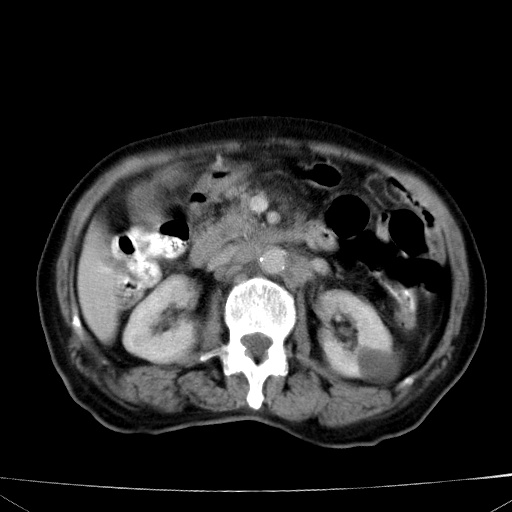

网站人气太旺!昨天的帖子就沉到海底,只好再发贴!ct18338:女 78岁,肝胆病变,已增强,再会诊!原帖链接:http://www.radida.com/bbs/forum.php?mod=viewthread&tid=50032

1)考虑胆囊癌侵犯肝脏并肝门区、腹膜后及右侧膈角后淋巴结转移。2)肝左叶近肝顶部囊肿。3)肝左叶肝内胆管结石。4)左肾近下极囊肿。